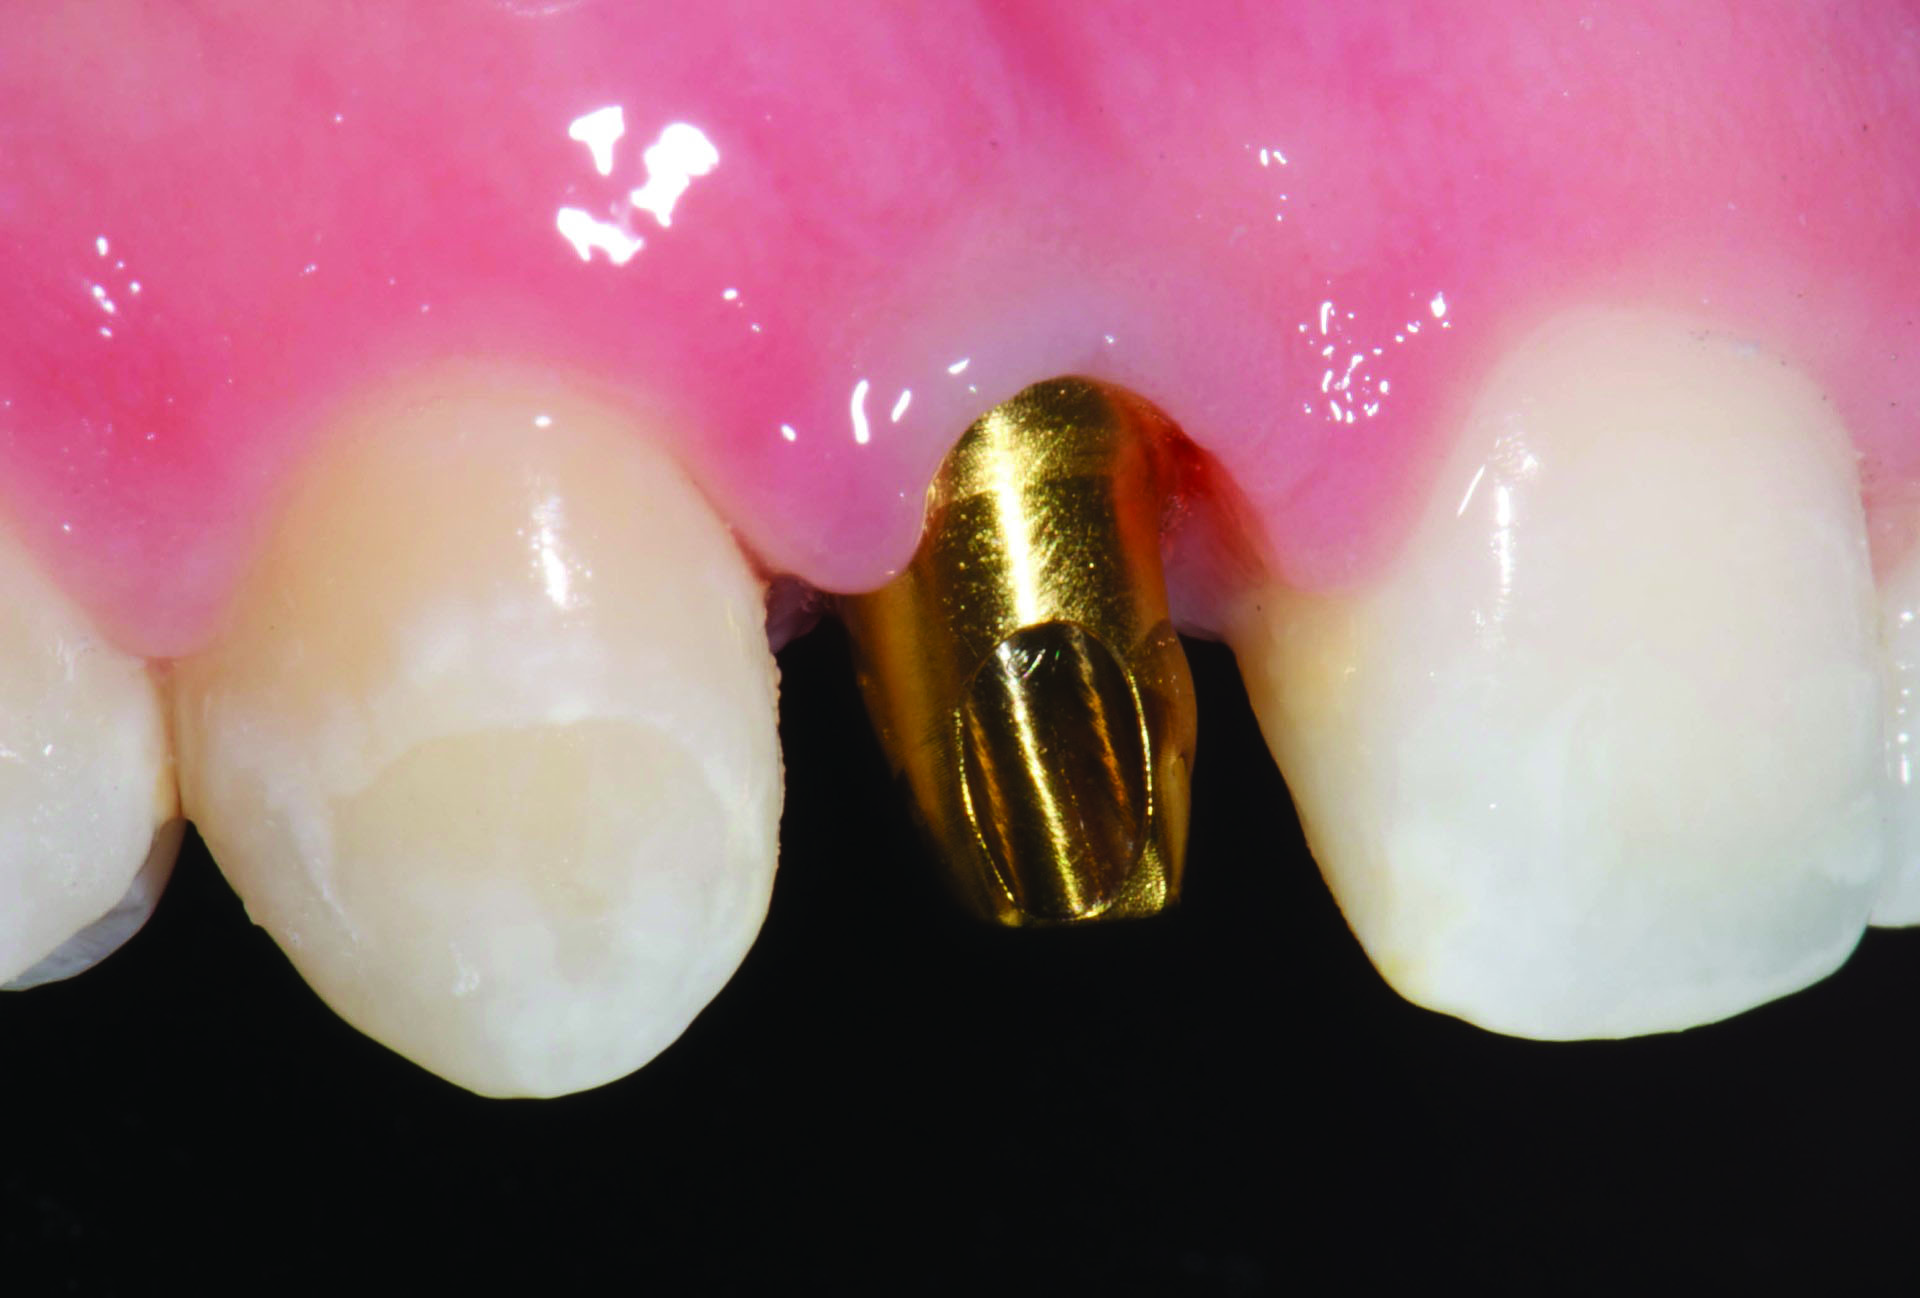

Fig 3. Gold anodized titanium custom abutment in preparation for crown cementation.

Figure 3

Figure 3 and Figure 4 show a gold anodized abutment and an overlying lithium-disilicate restoration, respectively. Zirconia is a relatively opaque ceramic, and studies are less clear as to the benefit of the use of gold anodized abutments under zirconia implant crowns. One study of 0.7 mm to 1.1 mm thick zirconia specimens reported that gold anodization of a titanium background did not improve the color match to a zirconia crown against a zirconia background.10 On the other hand, another study reported that the color change of 0.5 mm thick zirconia specimens against titanium backgrounds could be improved by gold anodization.11

An implant part can always be subjected to an additional soaking at a higher voltage to further change the color of the part; however, dipping at a lower voltage will not return the part to an original color. Therefore, it is prudent to start at a low voltage and observe the achieved color change when first attempting this procedure. An implant part can also attain more than one color by being selectively dipped in the solution. For example, an abutment could be dipped in solution at 60V to 65V to obtain a gold hue, and then the subgingival component of the abutment could be dipped in solution at 75V to 80V to gain a pink hue (Figure 7).15

Fig 7. Abutment with the subgingival component anodized pink and the coronal portion anodized gold, demonstrating the ability to achieve more than one color on the abutment as needed.

Figure 7

In summary, restoring a facially angled implant with a screw-retained angled screw channel crown or a crown with a zirconia abutment may lead to debonding issues of the crown from the titanium base. The use of a custom titanium abutment may avoid this technical complication. To overcome the esthetic challenge of placing a ceramic crown on a titanium abutment, the abutment can be anodized gold (60V to 65V) and then a 1 mm lithium-disilicate or 0.5 mm zirconia restoration would be able to acceptably mask the color of the abutment. If pink anodization of the abutment (75V to 80V) is needed to mask the color of the abutment under soft tissue, 1 mm of zirconia is needed to acceptably mask the color of the abutment. Preferably, in this clinical circumstance, the abutment could be selectively anodized at the subgingival portion only.